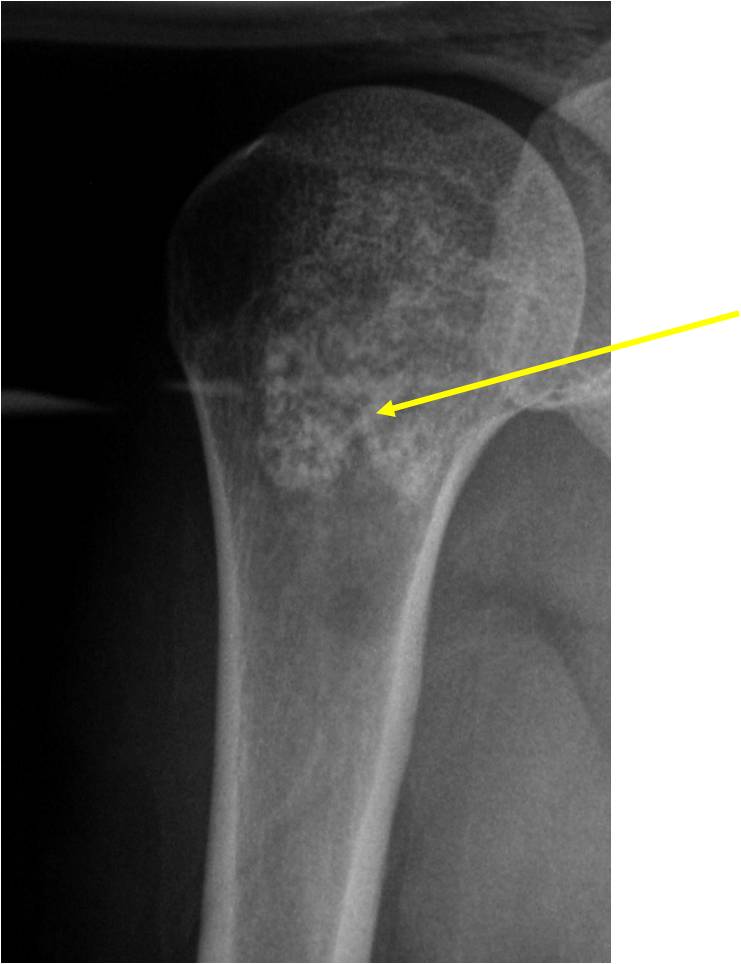

- Proximal Humerus, Femur most common long bones

Radiographic Presentation

- Localized, radiolucent defect usually with punctate calcifications

- Calcifications are typical but not always present

- Matrix may demonstrate various degrees of calcification

- Calcifications are stippled, punctate, popcorn like calcifications and “Ring and Arc” calcifications

- Cartilage tumors grow in a lobular manner. The perimeters of the lobules undergo

- enchondral ossification that may calcify. If the entire perimeter of the lobule calcifies it appears

- radiographically as a “Ring”. If a portion of the perimeter of a lobule calcifies it forms an “Arc” on

- an X-ray.

- May be located centrally or eccentrically

- Most commonly found in metaphysis

Plain X-Ray:

- Geographic lytic lesion

- Central often metaphyseal in long bones

- Expansile remodeling with thinned cortex

- Chondroid matrix with calcifications in majority of tumors

Metaphyseal Tumor, Heavy Calcifications, Ring and Arc Pattern of Calcifications, Minimal Endosteal Scalloping, No Cortical Destruction, No Periosteal Reaction, No Cortical Destruction, No Soft Tissue Component

Metaphyseal Tumor, Heavy Calcifications, Ring and Arc Pattern of Calcifications, Minimal Endosteal Scalloping, No Cortical Destruction, No Periosteal Reaction, No Soft Tissue Component